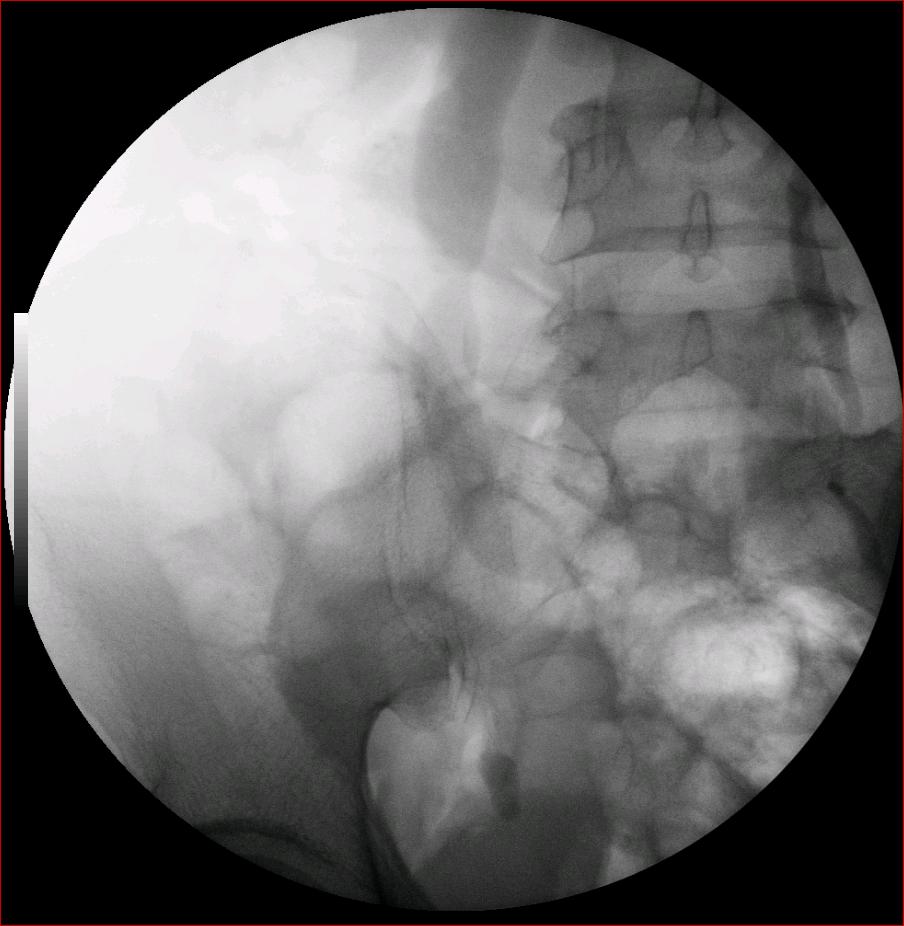

以下是引用luoxinjun在2008-2-18 15:54:00的发言:[br]右肾积水,右输尿管下端结石

以下是引用zhangxiangjun在2008-2-18 21:01:00的发言:[br]右输尿管盆段末端结石,继发其近端输尿管、右肾积水。

以下是引用hexue在2008-2-18 17:33:00的发言:[br]右输尿管下段结石并右肾及右输尿管积水扩张

以下是引用杀毒软件在2008-2-18 16:24:00的发言:[br]右输尿管下段结石,肾盂积水。